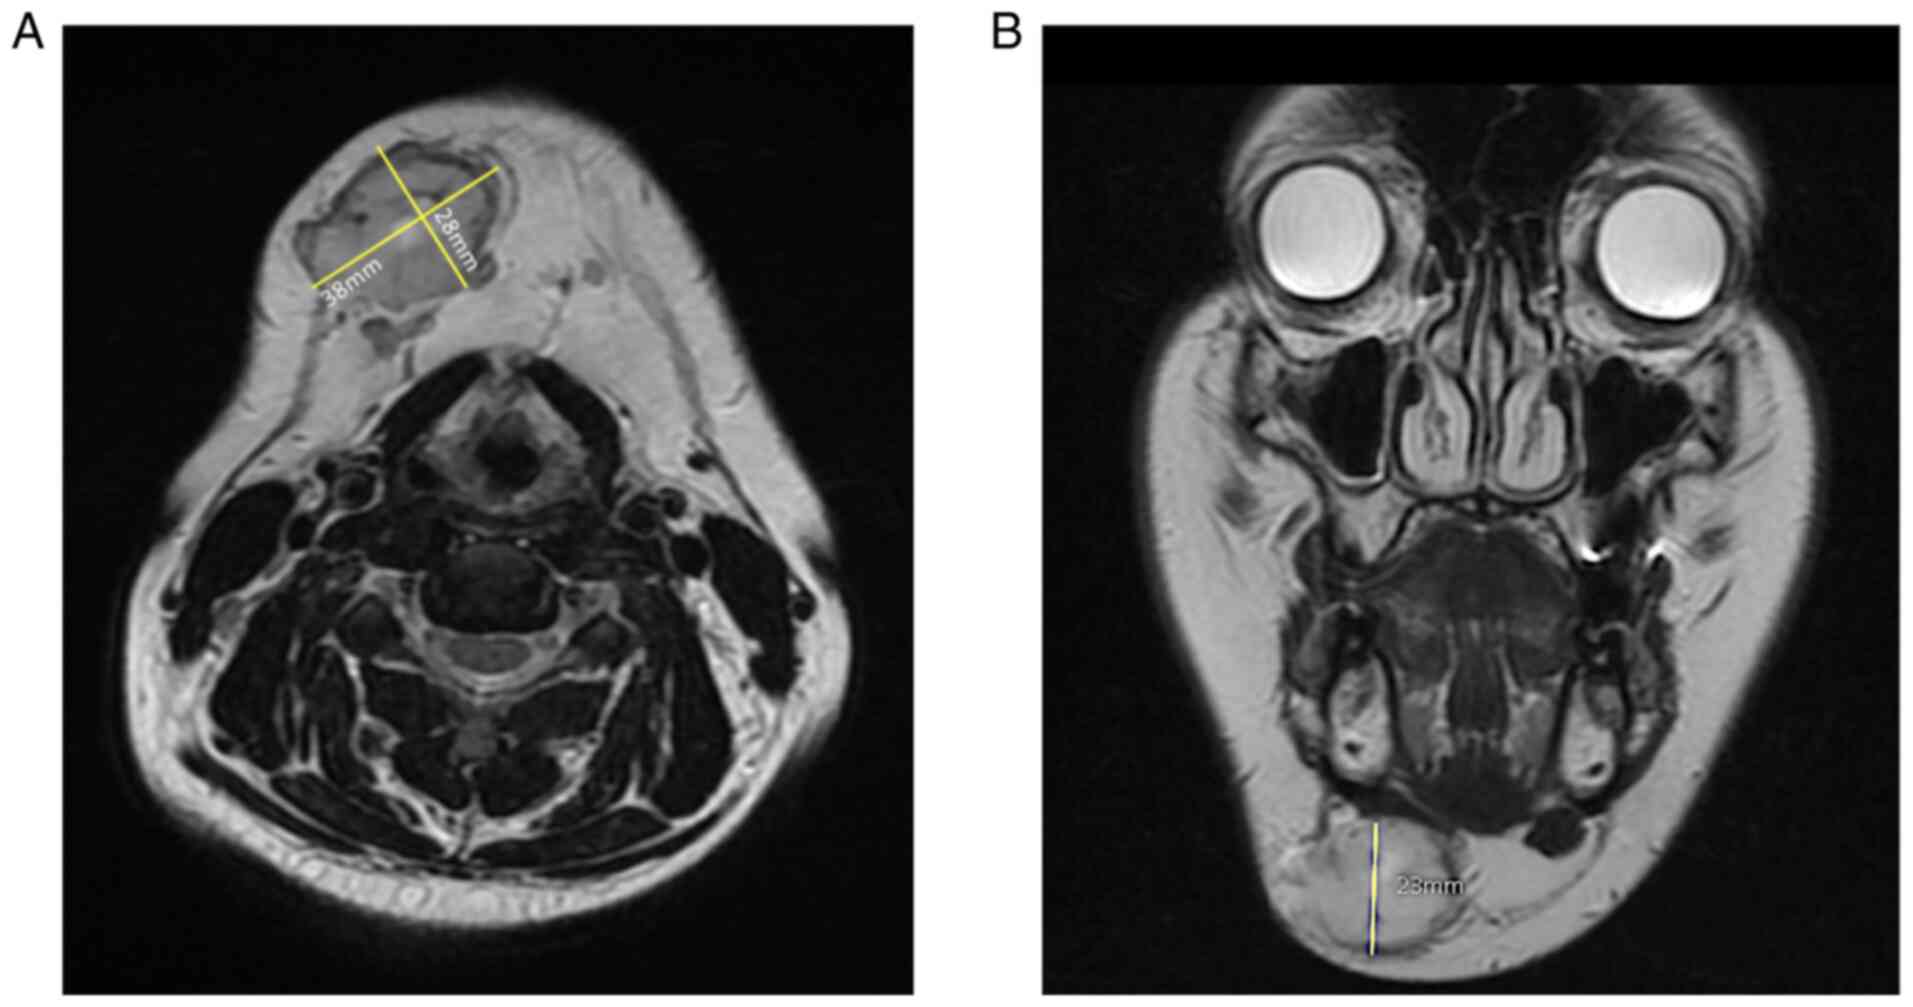

The first MRI was performed in June 2019, showing a solid nodular lesion measuring 25x21x20 mm, with a decreased signal intensity on T1 and increased signal intensity on T2-weighted images. After the diagnosis, the patient decided not to proceed with the surgery. She returned in October 2020 due to increased pain and a second MRI was performed, showing a significant growth of the tumor, measuring 38x28x23 mm; the enhancement pattern remained unchanged (Fig. 1).

During diagnostic evaluation an image test should be performed, with MRI being shown to be the most sensitive imaging modality for diagnosing glomus tumors (9,31). Most lesions are surrounded by a capsule and are iso- or slightly hyper intense on T1 and strongly hyperintense on T2-weighted images relative to the muscle, as seen on this patient (Fig. 1A). Vascular predominant GT could show a stronger contrast enhancement (31-34).